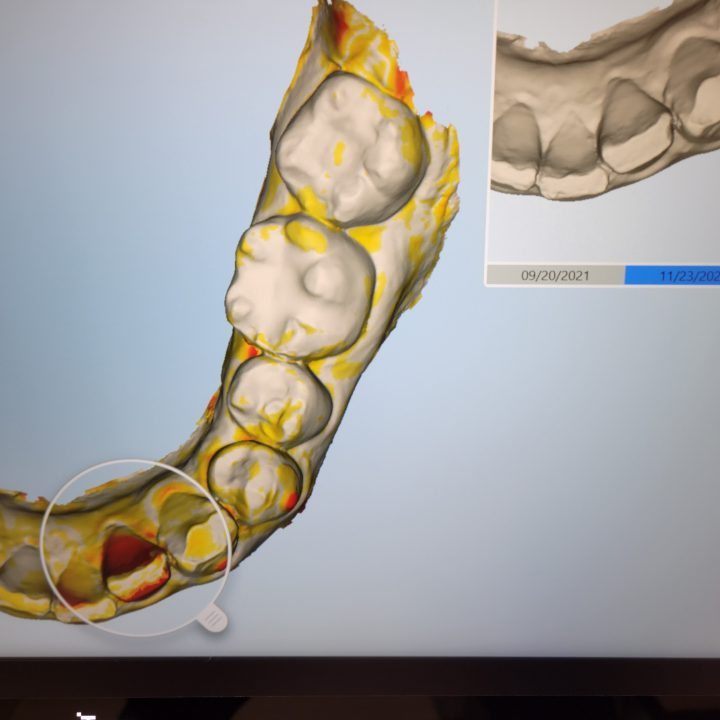

↑これはiTeroのNIRIモードを使用したスキャナーデータです。

右上のレントゲンのような白黒の画像(NIRIモード)では、

歯と歯の間、真っ白に写った部分、

虫歯、もしくは虫歯になりかけているところを診ることが出来ます。

虫歯を可視化できる一つのツールです。

中には、すぐに削る必要がない経過観察をしてもよい歯もあります。

が、肉眼では分かりにくい場合など、初期の診断に有効です。

実際、削ってみると

エナメル質の下に虫歯がありました。

さほど大きな穴ではなかったので、樹脂(レジン)にて修復して終わりです。

時間が経過していると痛みを伴う虫歯になる可能性もありました。

歯は出来るだけ削りすぎないのがよいので

MI治療(最低限の侵襲)で、なるべく修復したいです。